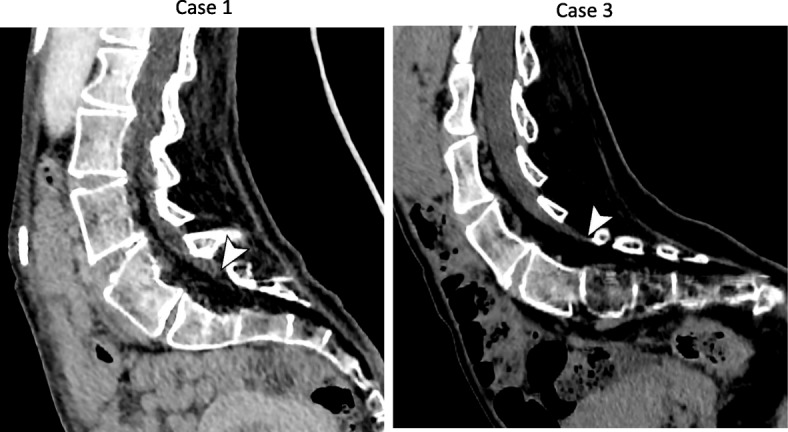

Fig. 2.

Curved multiplanar reconstructed images in 2 cases (cases 1 and 3). Arrowheads indicate the lower end of the dural sac

Cerebrospinal fluid outflow was not detected after inserting the needle from the L4/5 or L5/S1 interspaces (depth 70 mm), despite the location of the tip of the needle in the spinal column on the fluoroscopic image. Further, examination of CT revealed that the dural sac terminated at the L5 level (Fig. 2). Although the L3/4 was in a difficult position to confirm the laminar spaces on CT, the needle was inserted there (depth 70 mm), cerebrospinal fluid (CSF) outflow was confirmed, and nusinersen 12 mg (5 mL) was administered intrathecally after collection of 5 mL of CSF.

Patient 3 was a 17-year-old girl (139 cm, 22 kg) with a diagnosis of SMA type 1 at the age of 11 months. Three-dimensional CT demonstrated that the lumbar spine was markedly rotated, and performing puncture was expected to be difficult (Fig. 1). Images obtained before the procedure confirmed that the dural sac terminated at the L5 level (Fig. 2); therefore, the needle (25 G × 70 mm) was inserted into the L3/4 (depth 45 mm), and nusinersen 12 mg (5 mL) was administered intrathecally after collection of 5 mL of CSF. There were improvements in motor function of extremities after second administration in all cases.

In our three patients, the tip of the needle was inserted into the spinal column, but outflow of CSF was unable to be confirmed. One of the common causes for the lack of CSF outflow is needle tip placement outside the subarachnoid space [9]. The dural sac terminates at the S3–S4 level during the neonatal period and is considered to shift to the S1–S2 level by the age of 1 year [10]. Cadaver, magnetic resonance imaging, and myelographic studies revealed that the dural sac terminates most often at the S2 level, but this location can vary from the L5/S1 to the S4 levels [11–13]. On CT, the dural sac terminated at the L5 level in 2 of our patients and at the L5/S1 level in 1, which were higher levels than normal, and this may have been the reason for the absence of CSF outflow. In these circumstances, even if the tip of the needle was in the spinal column, the lower end of the dural sac may have shifted and tapered, and the tip of the needle may have been located outside the subarachnoid space.